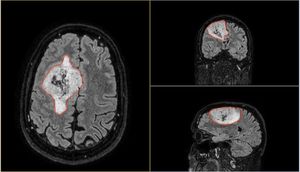

I believe there are around 4,000-5,000 images in total from 1 CT and 1 MRI scan! Thankfully there are tools that you can use to view these images. And not just view them, they allow you to navigate through all the scans. Each image is essentially a "slice" of the brain. The tools allow you to move through all 3 axis in near real time, with each of the corresponding panels changing depending on the input from the others.

In the above image you can see my MRI scan. It's essentially an orthogonal view of my head, with each of the panels represents a different axis:

- Left panel: Top of my head (Axial view)

- Top right: Front to back of my head (Coronal view)

- Bottom left: Side of my head (Sagittal view)

The solid blue line you see in the views is the current plane I have selected to see. As you move this plane, all three images change accordingly. Notice how the blue line on the axial view (left panel) matches that of the coronal view (top right) in terms of position. The resulting image in the sagittal view (bottom left) is the image that corresponds with this selection I have made.

It's so incredibly clever and absolutely fascinating (to me at least)! I spent the best part of 2-3 hours looking at my own brain scans. I wish I knew what it all meant, but I plan on quizzing the experts when I get the chance. I'd like to write a blog post all about it in the future. So, watch this space!